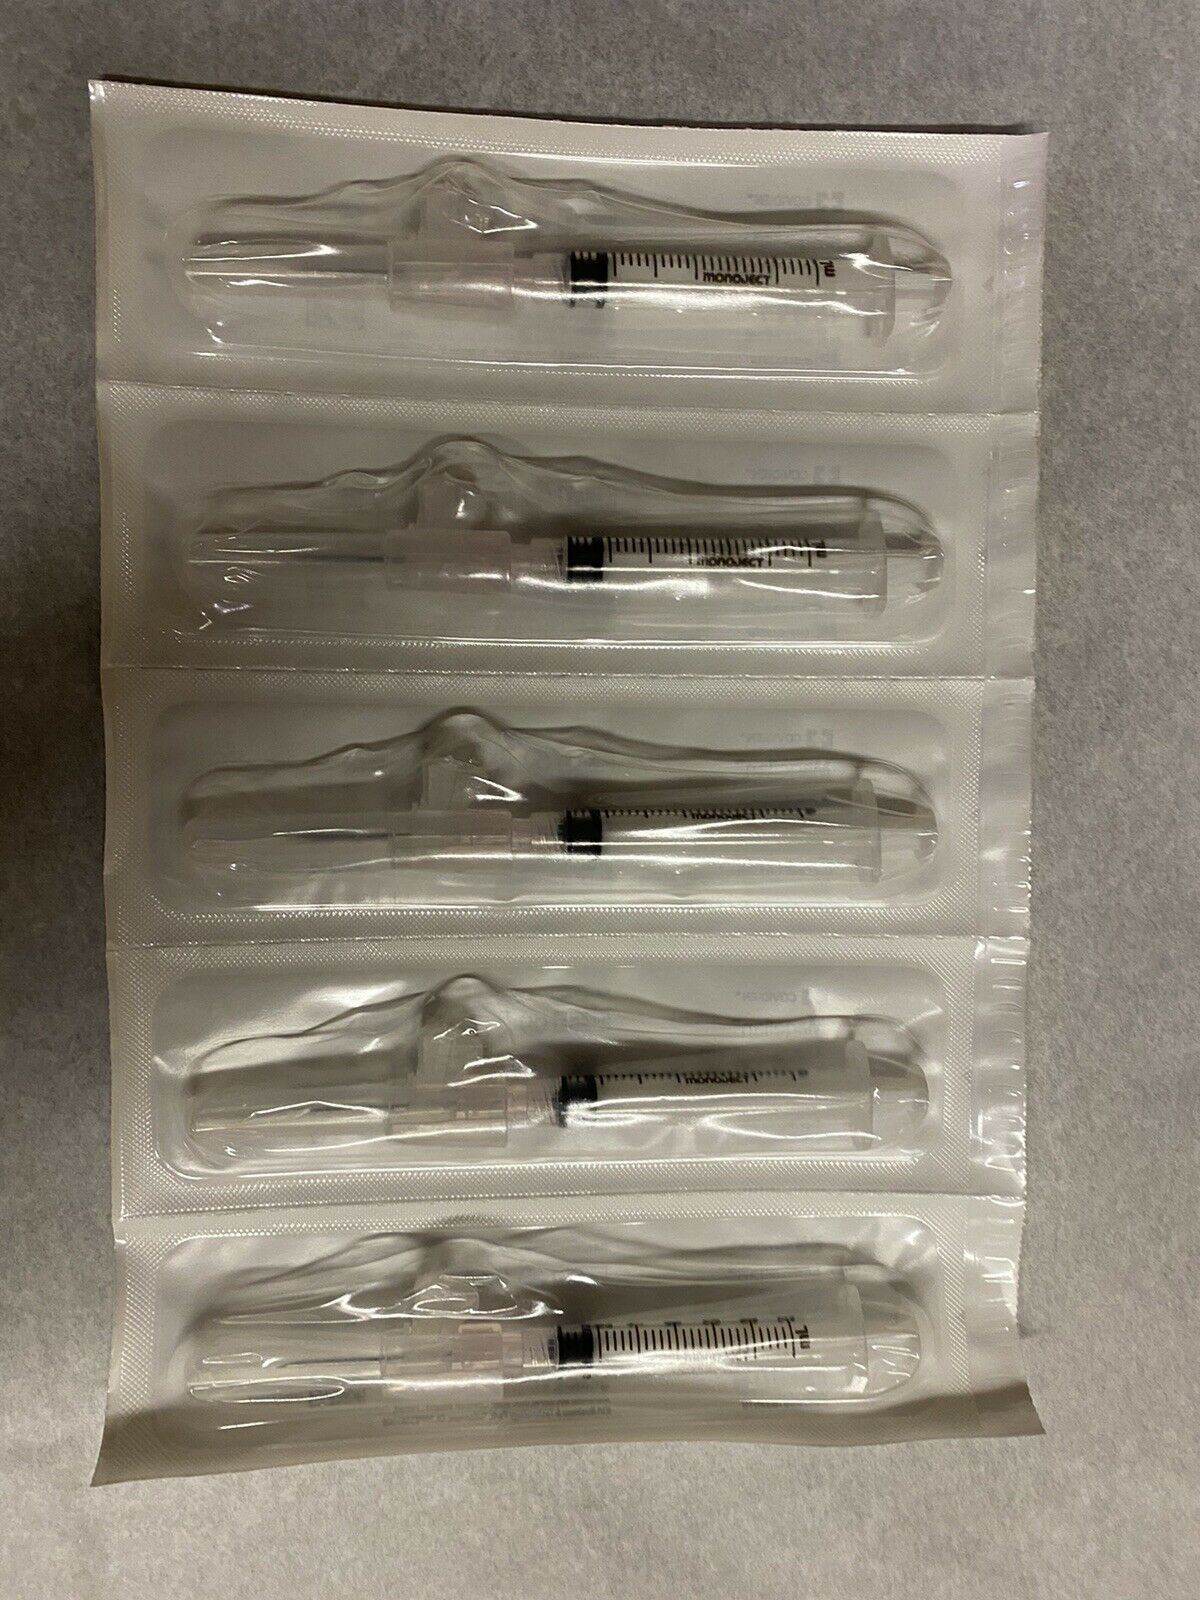

Save $ 5.40

DIAGNOSTIC ULTRASOUND MACHINES FOR SALE

BRAND NEW 3ml(3cc)1 box of 50 Syringes

Sale price$ 24.59

Regular price$ 29.99